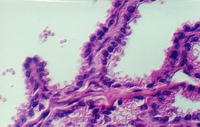

The lumen of this gland is thrown into many folds that appear to branch. This creates a labyrinth of channels, tubes, and pockets into which the secretory product flows. The epithelium shown in the photos below may be simple columnar with patches of pseudostratified epithelium. The appearance of the epithelium is variable and dependent on age and the level of androgen production. One can see some lipochrome pigment in the epithelium, which is present in elderly males. Look at the wall of the gland and again, there are numerous bundles of smooth muscle.

What does the seminal vesicle contribute to the semen?